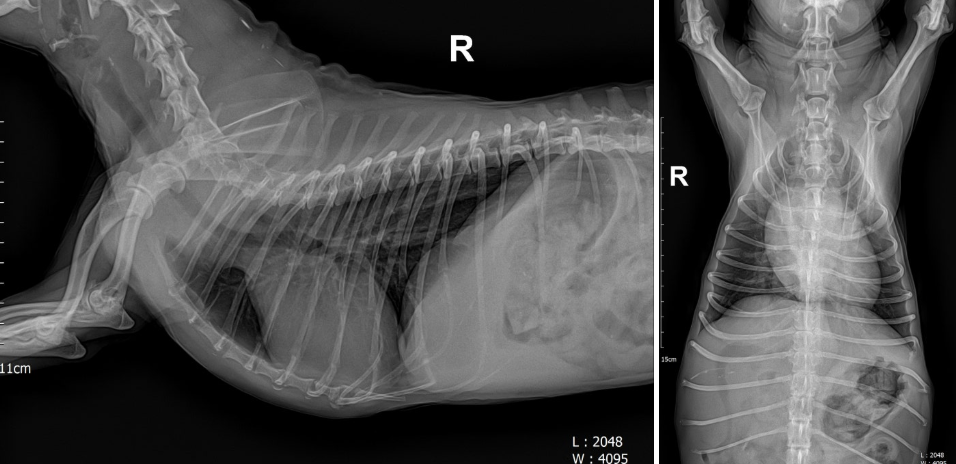

이를 위해 수술 전 흉부 X-ray 검사를 시행해 심장 크기와 폐 상태를 확인했고, 마취 및 수술 과정에서 문제가 될 수 있는 요소가 없는지 점검했습니다. 이 과정은 강아지 백내장 수술의 안전성을 높이기 위한 필수 단계입니다.

(수술 전 흉부 X-ray)